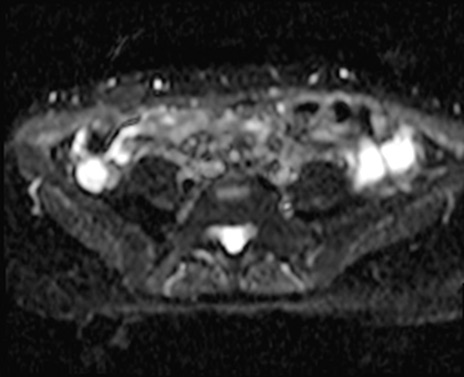

MRI(4日後)